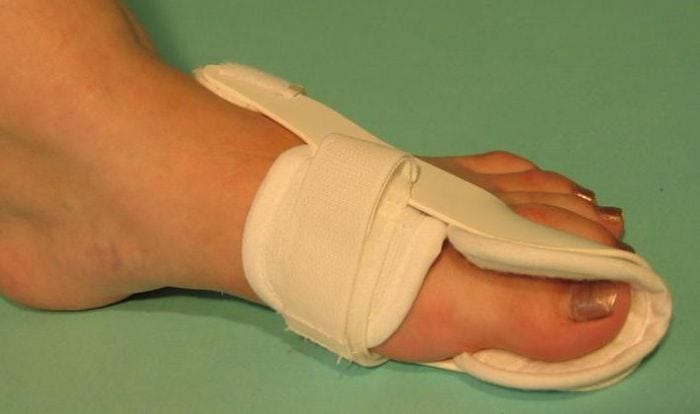

С самого начала лечения пациентам показано ношение специальных ортопедических приспособлений для обеспечения правильного анатомического положения стопы. Используются межпальцевые вкладыши, супинаторы, накладки различной жесткости, предупреждающие дальнейшую деформацию плюснефалангового сустава. Ортопедические приспособления также помогают избежать развития воспалительного процесса из-за натирания мягких тканей.